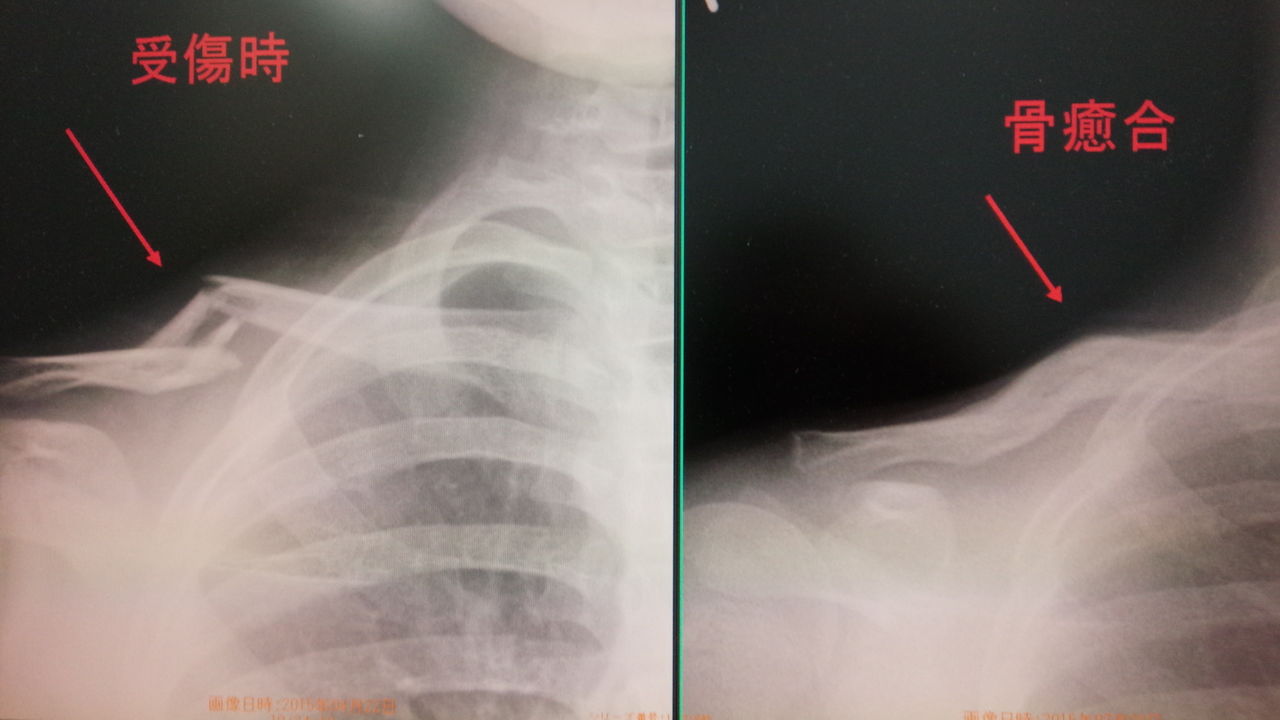

最近は 鎖骨骨折 は  手術することが すくなくなりました

骨膜反応が強いですね   手術いらず

右鎖骨骨折                      サッカー

左鎖骨骨折                      ライダー

イメージ 2